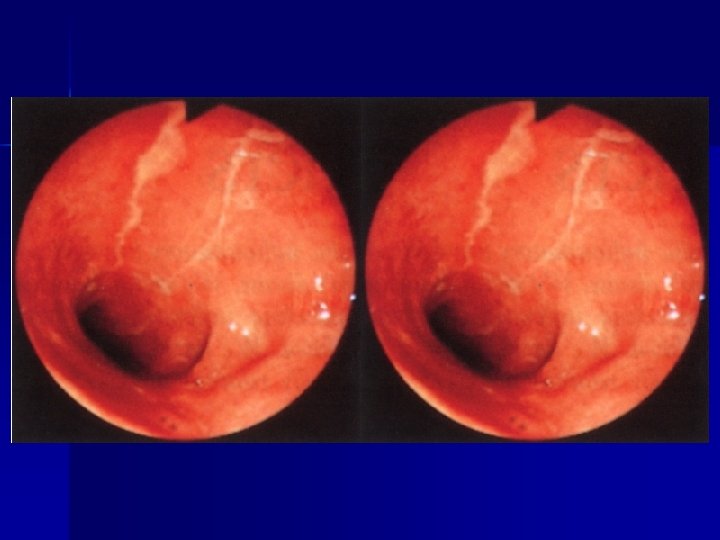

ENDOSCOPIA Lesioni del basso esofago n Patologia gastroduodenale(gastrite, ulcere, ernia iatale, corpi estranei) n Patologia rettocolica (colite ulcerosa, aspecifica, allergica, m. di Chronn) n